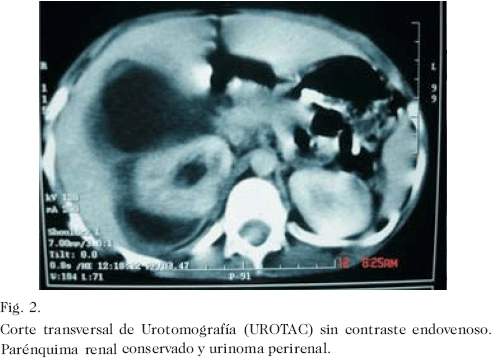

Escolar masculino de 6 años de edad quien acudió a la emergencia del Hospital Universitario de Maracaibo, 1 hora posterior a presentar contusión lumbar derecha al caer sobre su altura, que ocasionó dolor local de fuerte intensidad y hematuria macroscópica. El examen físico reveló paciente en regulares condiciones generales, con moderada palidez cutáneo-mucosa, pulsos periféricos débiles, 139 pulsaciones y 32 respiraciones por minuto. La valoración abdominal evidenció dolor a la palpación desde hipocondrio hasta fosa iliaca derecha, con contractura muscular voluntaria. Se indicó expansión vascular con solución de Ringer Lactato, a razón de 20 mL kg/peso. Sus condiciones hemodinámicas se mantuvieron estables. Se indicó hidratación de mantenimiento. La hemoglobina descendió 3,1 g% en las primeras 48 horas. Se indicó concentrado globular cuando las cifras de hemoglobina descendieron hasta 6,8 g%. Se realizó eco-doppler renal al ingreso en la emergencia que reportó compromiso de parénquima derecho con presencia de flujo vascular y colección peri renal (Fig. 1). Se practicó tomografía computadorizada simple 10 días posteriores al ingreso; en los cortes sin contraste (Fig. 2), se comprobó la colección observada en el ecograma. Cuando se administró contraste endovenoso, se evidenció extravasación del material de contraste al espacio retroperitoneal derecho (Fig. 3). A los 16 días del accidente se drenó el urinoma en quirófano con un nefrostomo percutaneo calibre 14 Fr. en región lumbar derecha no dirigido por ultrasonido ni tomografía, obteniéndose un litro de orina. La evolución clínica fue satisfactoria, egresando una semana después con catéter de drenaje. A los 43 días del accidente y a los 27 días de haber colocado el nefrostomo, se retiró en quirófano. Seis meses posteriores al traumatismo el paciente se encuentra sin síntomas y libre de complicaciones. En la urografía de eliminación realizada 4 meses posteriores al trauma, se observó parénquima renal funcionante, con leve alteración de arquitectura del sistema urinario excretor y buena eliminación a través del mismo (Fig. 4).